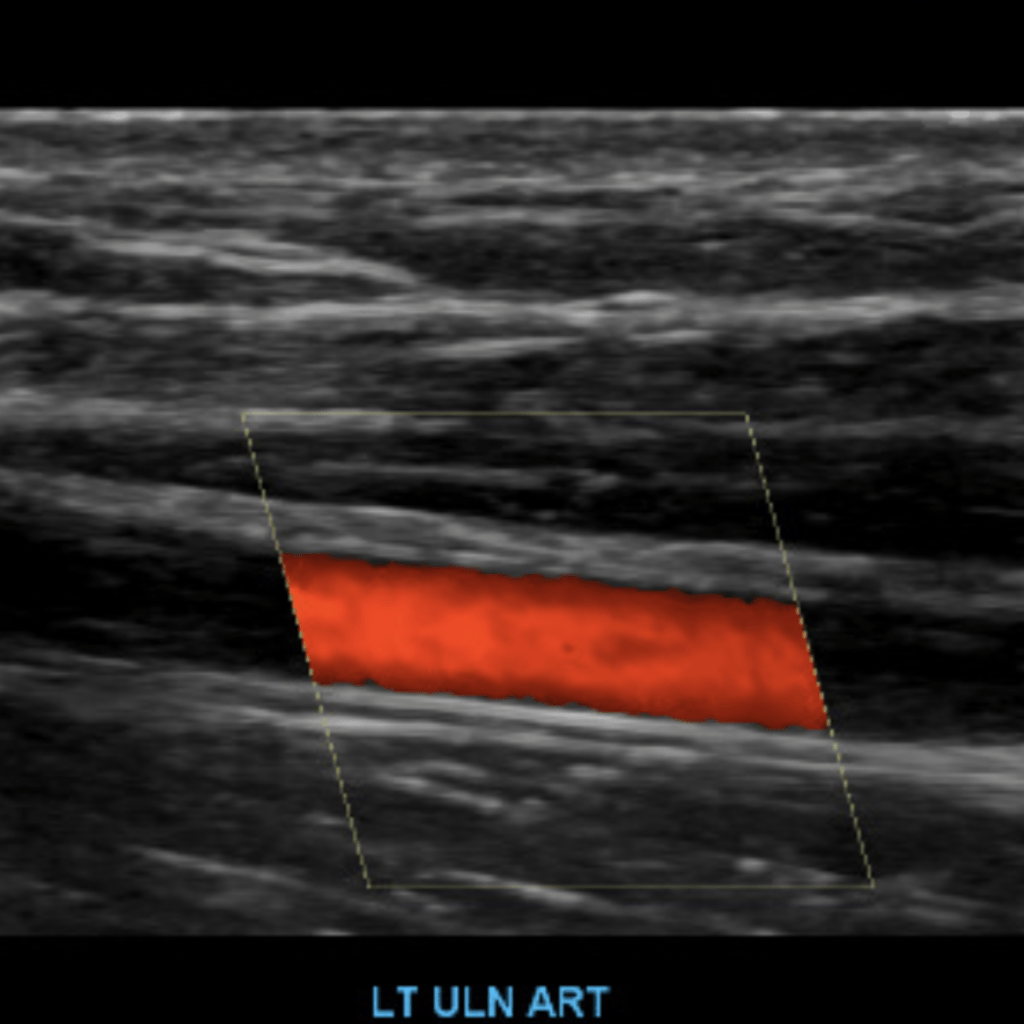

The subclavian artery arises from the brachiocephalic artery on the right and off of the aortic arch on the left. This artery further divides into the axillary, brachial, radial, ulnar, palmar and digital arteries respectively.